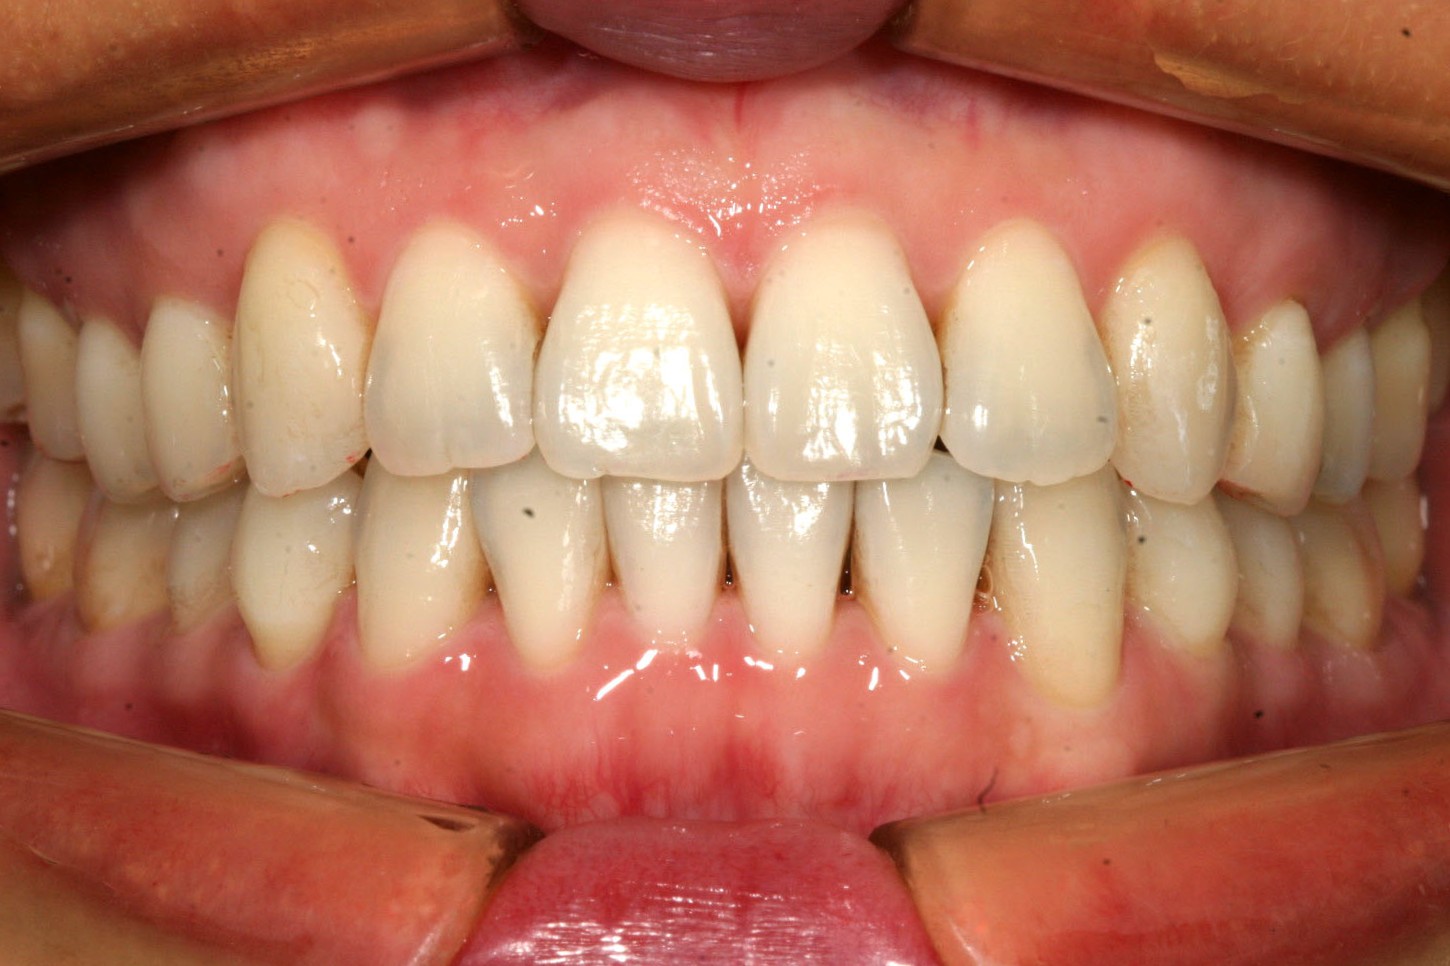

右側の犬歯の飛び出しが目立ちます。

アーチを広げ綺麗に改善しました。